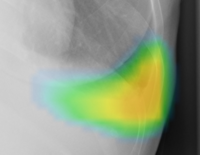

左:オリジナル画像/右:解析画像

(2)ヒートマップ/輪郭表示機能

異常所見の存在可能性(確信度)を,青から赤へのグラデーションで示すヒートマップ表示について,多くの利用者から好評を得ている。一方,モノクロモニタを利用する一部の読影環境では,淡いヒートマップが確認しにくいという課題があった。新バージョンでは,異常所見の疑われる領域の表示方法として,「ヒートマップ表示」「輪郭表示」「ヒートマップと輪郭の併用表示」の3つの表示パターンが選択可能になった。これにより,各施設の運用環境に応じた最適な表示方法を利用できる。